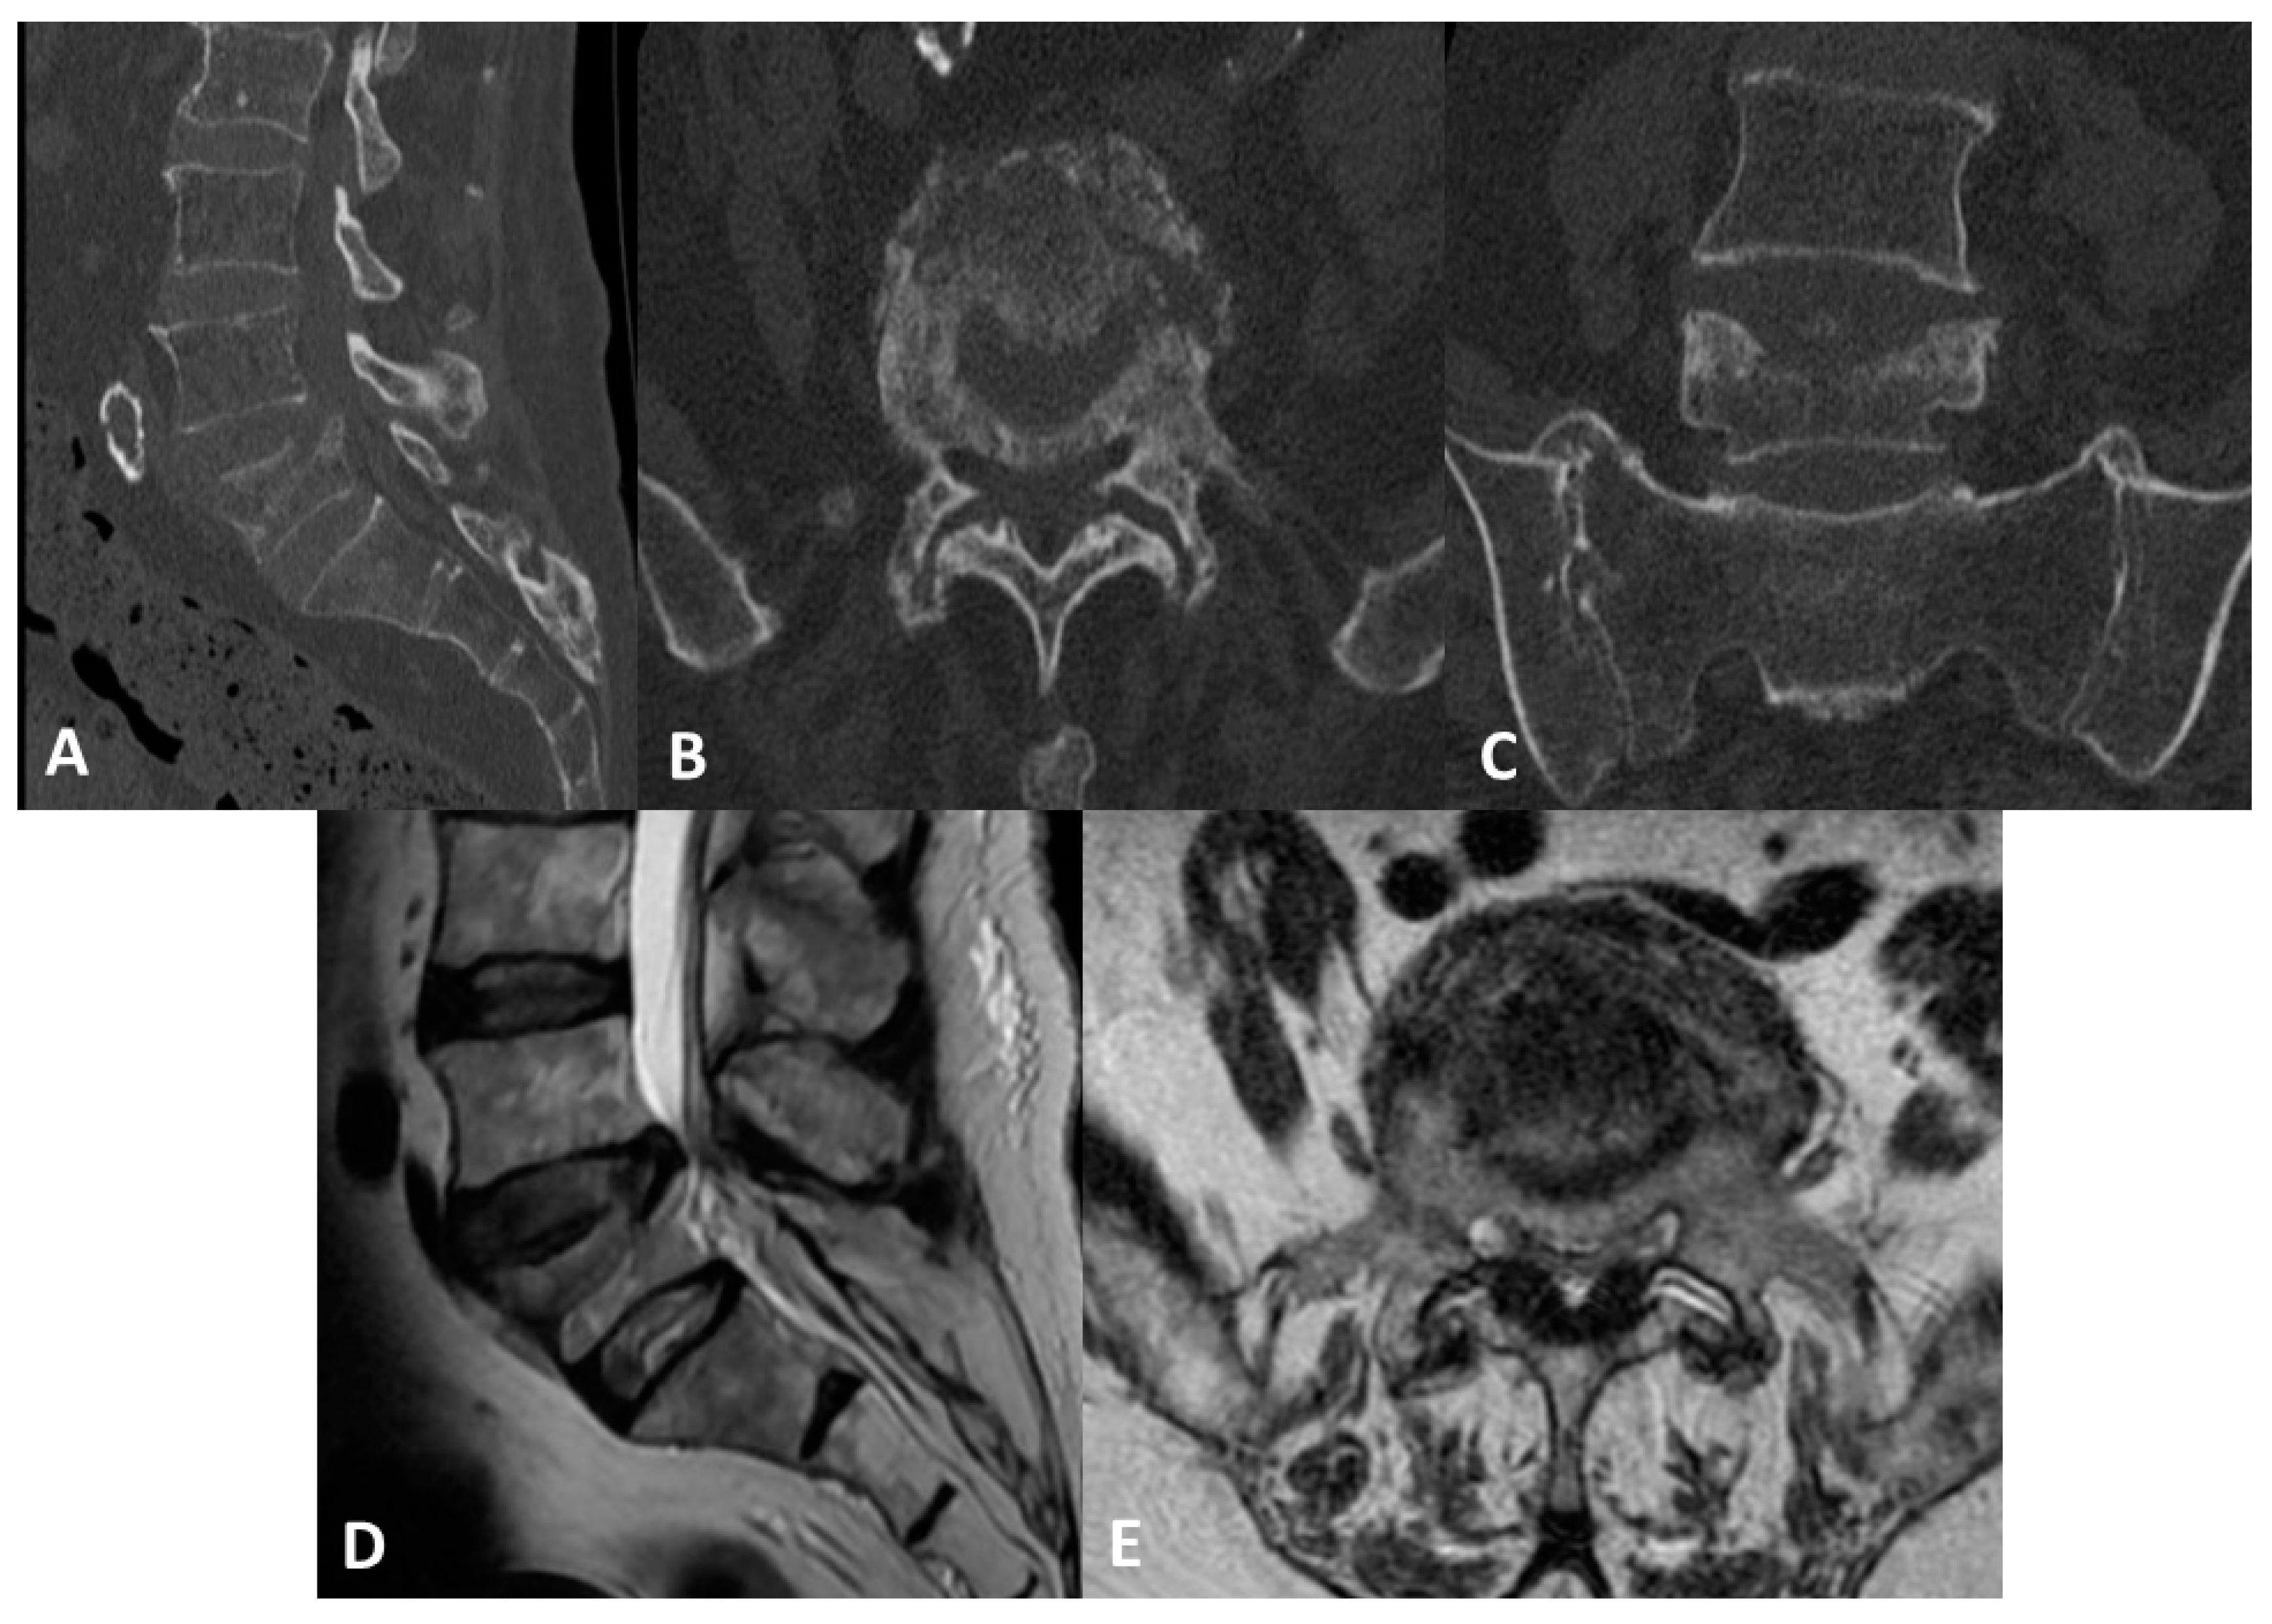

2. Case Report